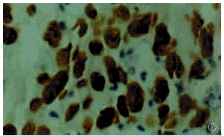

图6 胃癌组织中p53蛋白的表达(40×10)

利用显微分离和巢式PCR相结合的技术,逐个对4%甲醛固定、石蜡包埋的171例标本进行了p53外显子5、6、7、8的突变研究,有70例获得较满意的结果,总成功率为约41.0%。其中早期胃癌6例,占22例早期胃癌总数的27.3%;进展期胃癌64例,占149例进展期胃癌总数的43.0%。

2.2胃癌组织中p53蛋白的表达

见图6说明,p53阳性反应物质均位于核内。在检测的70例胃癌标本中,有33例p53蛋白阳性,包括3例早期胃癌和30例进展期胃癌,阳性率为47.1%。